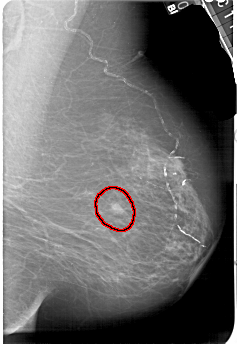

A_1511_1.RIGHT_CC

RIGHT_CC LINES 5491 PIXELS_PER_LINE 3736 BITS_PER_PIXEL 12 RESOLUTION 43.5 OVERLAY

FILE: A_1511_1.RIGHT_CC.OVERLAY

TOTAL_ABNORMALITIES 1

ABNORMALITY 1

LESION_TYPE MASS SHAPE IRREGULAR MARGINS ILL_DEFINED

ASSESSMENT 4

SUBTLETY 4

PATHOLOGY MALIGNANT

TOTAL_OUTLINES 1

BOUNDARY